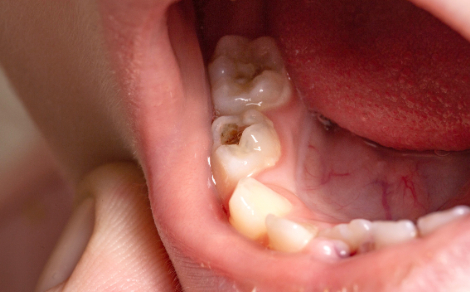

一方、3歳以上、特に6歳臼歯が生えてくる年齢になると、臼歯の溝(小窩裂溝)が虫歯になりやすいです。

特に学齢期になって自分で歯磨きをするようになると、歯ブラシがなかなか奥まで届かないことや磨く場所が偏ることから、臼歯の溝が虫歯になる子どもが増えるのです。